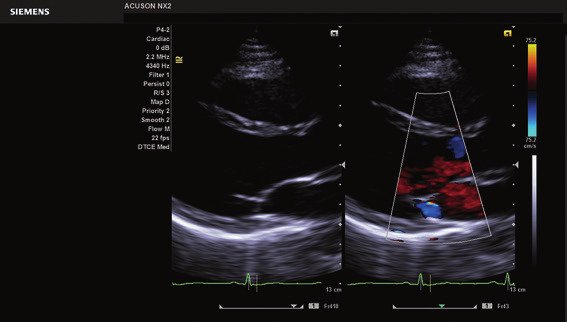

• Color, Power Angio, PW (Pulse Wave) Doppler

Das ACUSON NX2 Ultraschallsystem besitzt eine zukunftsfähige digitale Plattform mit nahezu unerreichter Bildqualität und sorgt für effiziente und zuverlässige Diagnosedaten. Die Vielseitigkeit des Ultraschallsystems wird mit einem großen kompatiblen Portfolio an Schallköpfen gedeckt, und so ist für jeden Anwendungsbereich etwas dabei. Die Bedienkonsole ist intuitiv aufgebaut und optimiert und erlaubt bis zu vier nach vorne gerichteten Schallkopfanschlüssen für eine enorme Effizienz und schnellen Workflow. So lassen sich bei der fetalen Bildgebung außergewöhnlich detailgetreue Darstellungen des Fetus im Gesicht zeigen oder durch die herausragende Farbdopplersensitivität bei der Darstellung der kleinen Gefäße des zystischen Schilddrüsenknotens kleinste Details erkennen. Weiterhin besticht das NX2 mit einfacher Aufrüstbarkeit bei wachsenden Anforderungen für Ihre zukünftigen Anwendungen und kompatible skalierbare Schallköpfe verringern ihren Kapitaleinsatz um bis zu 31 %.

• Kardiologie